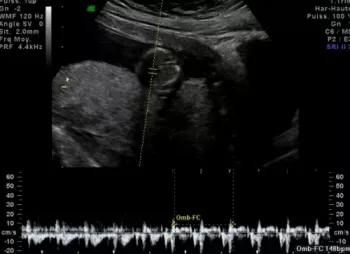

DES ULTRASONS, TOUT SIMPLEMENT...

L’échographie utilise des ultrasons émis par une sonde et transmis dans les tissus qui les réfléchissent pour former une image de la région examinée. Elle peut être couplée à une sorte de radar pour l’étude des vaisseaux (doppler).